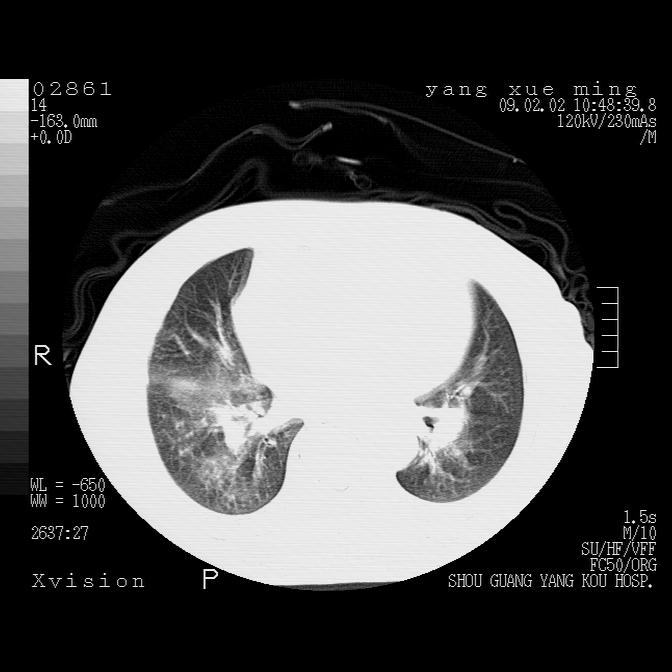

以下是引用lkc8963在2009-2-3 20:11:00的发言:[br]1)右上肺陈旧病灶。2)右下肺团块及团片影,影像表现符合感染。3)左心增大,左冠脉钙化,符合冠心病。4)双侧肺门扩大,以左侧为著,肺动脉干略粗,左上肺局限性气肿,为谨慎起见,需除肿瘤,建议增强。

以下是引用zbp537在2009-2-3 19:08:00的发言:[br]我诊断为肺泡性肺水肿。[br]诊断依据:[br]1、心影普遍增大,肺血管增粗,并见絮状高密度影,肺门改变显著。[br]2、临床上表现胸闷咳嗽,无发烧,不是一个典型的肺部感染的病史。

以下是引用王仕学在2009-2-3 20:28:00的发言:[br]考虑右下肺感染,建议治疗后复查。